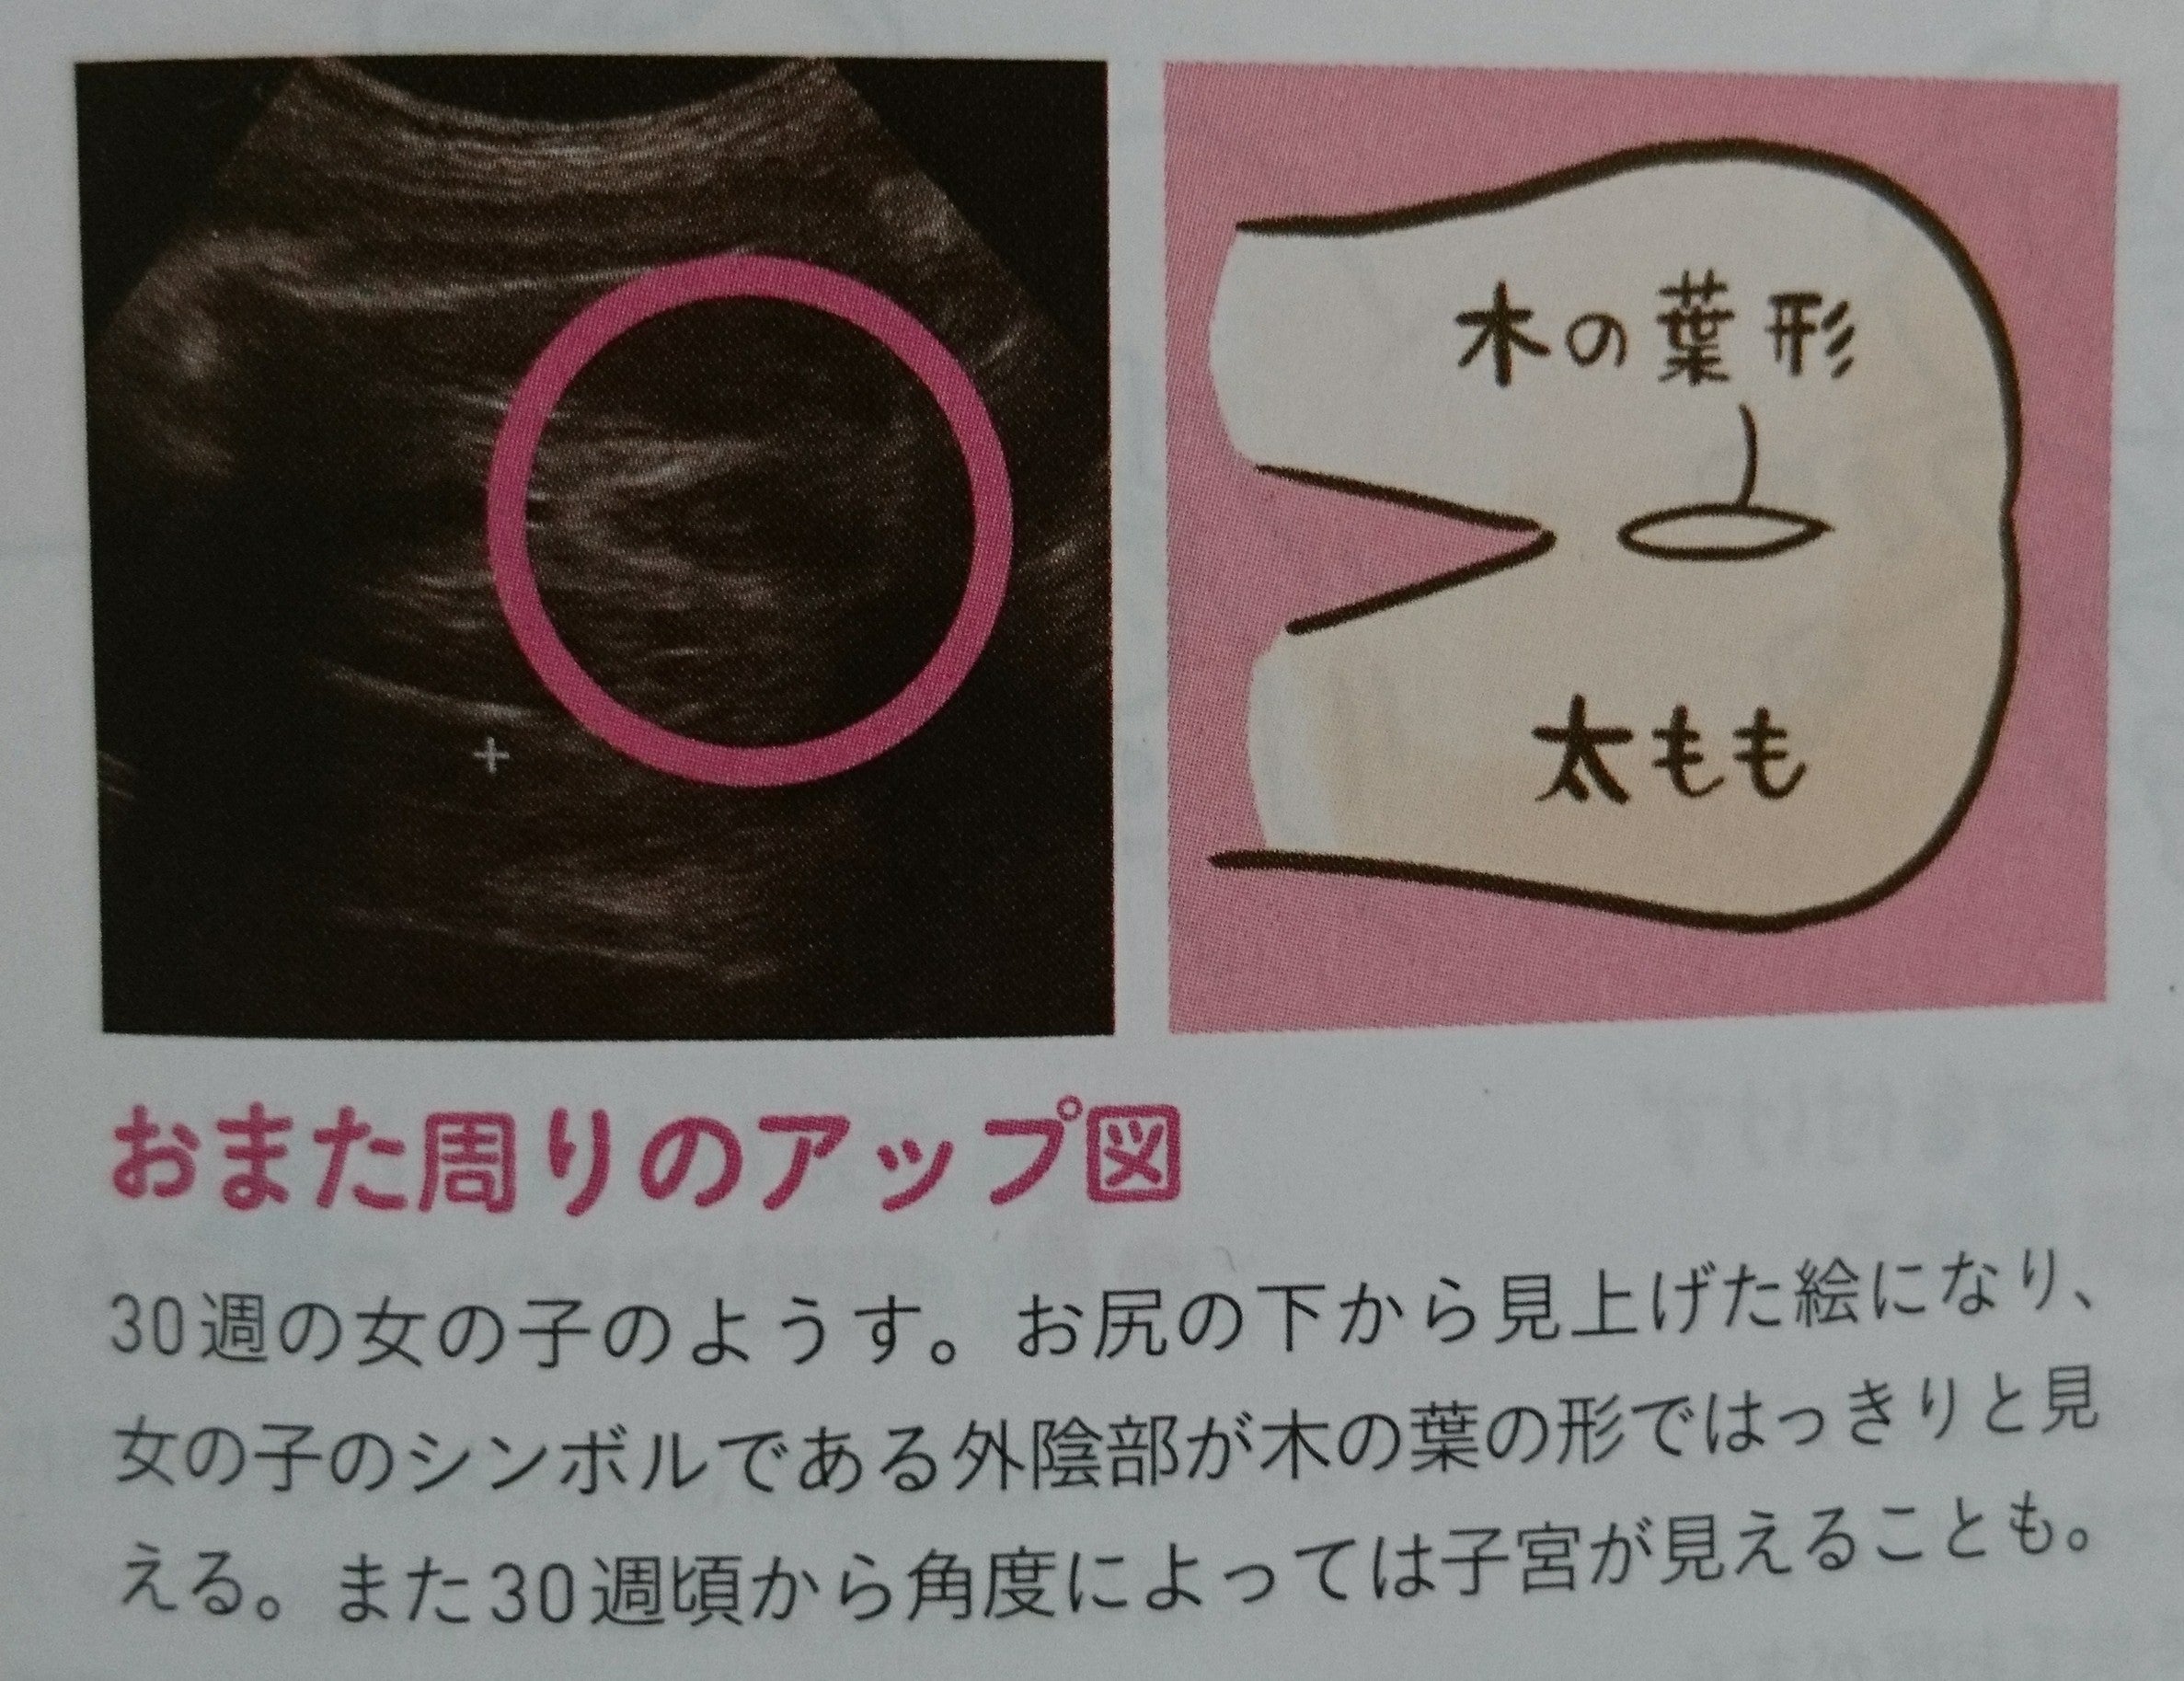

東京 テアトル 評判~杖 イラスト 無料;. 残念ながら我が家に女の子はいないので、とてもわかりやすい画像をゼクシィbabyよりお借りしました。 女の子の場合、 会陰部に”木の葉マーク”や”コーヒー豆”のような真ん中に何かしらの線が入っていることで判断 されます。. 解決済み 質問日時: 2014年2月2日 18:43 回答数: 1 閲覧数: 671.

女の子 の場合は、突起物はなく、 太ももの間に 木の葉のようなもの が見えます。 また、子宮と膀胱がふたつの黒い点として エコー写真に写ります。 ※女の子に恵まれれば、いつか写真参考アップしますね٩(•౪• ٩).